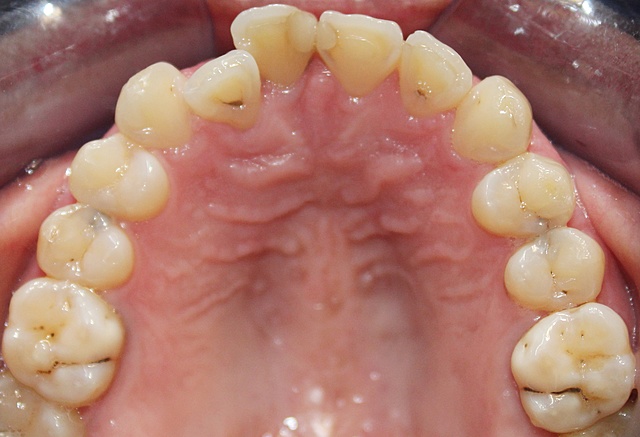

• Análisis intraoral

Análisis intraoral

Se encontró un apiñamiento leve, restauración filtrada en OD 1.1 y 2.1. Caries en OD 1.2, 1.5 1.6, 1.7, 1.8, 2.2, 2.4, 2.5, 2.6, 2.7, 3.4, 3.5, 3.8, 4.5, 4.7 y 4.8. Ausencia de OD 3.6, 3.7 y 4.6.